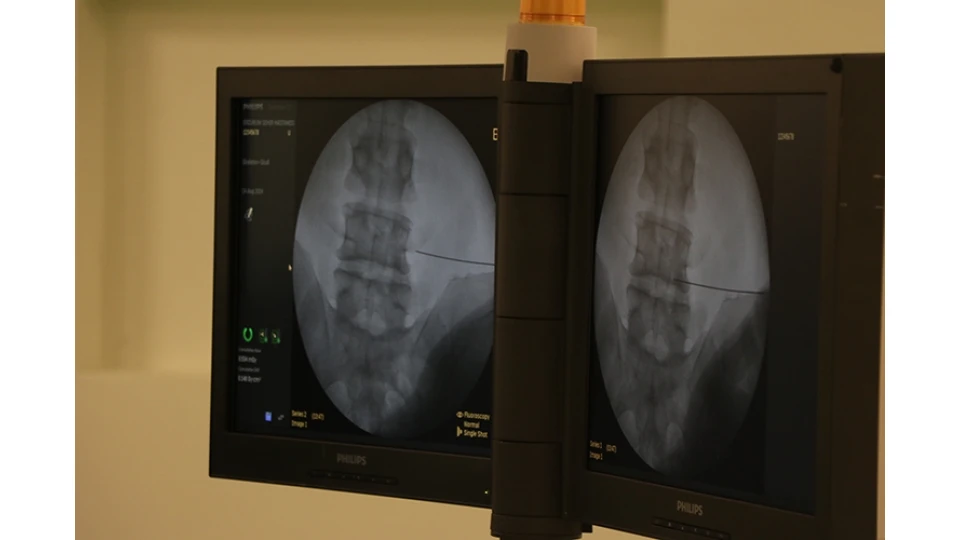

5. Bel Fıtığı (Lomber Disk Hernisi)

Omurlar arasındaki disklerin yerinden kayarak sinirlere baskı yapmasıyla oluşur. Bel ağrısı, bacaklara vuran ağrı, uyuşma ve güç kaybı gibi belirtilerle kendini gösterir.